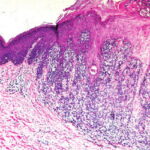

component may be considered also in this category . The ABCD criteria reviewed earlier do not apply to nodular melanomas, which often present clinically as quite small, symmetric, and well-circumscribed papules or nodules . These may be conspicuously pigmented, oligomelanotic, or even amelanotic. The tumorigenic nodule that may develop in nodular melanoma does not differ clinically or histologically from that which may occur in relation to a preexisting nontumorigenic melanoma. Indeed, nodular melanomas may represent examples of telescoped tumor progression in which the antecedent radial phase has been so short lived as to be unapparent . The clinical importance of the nodular subtype has been emphasized recently; these lesions are more likely to present at a biologically advanced stage despite a comparatively short clinical history . The mutation profile of nodular melanoma is closer to that of superficial spreading melanoma than to the other subtypes, in that BRAF or NRAS are commonly mutated . |

Histopathology of Nodular Melanoma and Common Vertical Growth Phase (Tumorigenic Melanoma) Architectural Features. In a typical tumorigenic melanoma, there is contiguous proliferation of neoplastic melanocytes in the dermis forming a tumor mass that is larger (usually much larger) than the largest nest in the |

Perhaps the best-known single criterion for melanoma is the upward pagetoid extension of tumor cells into the epidermis overlying the melanoma. However, this pagetoid melanocytosis or pagetoid spread is not specific for melanoma (152). Although in nodular melanoma, permeation of the epidermis with tumor cells may be absent or may be limited to that portion overlying the dermal tumor, lateral extension of melanoma cells in the epidermis and papillary dermis beyond the confines of the dermal tumor is seen in the adjacent nontumorigenic compartment of complex primary melanomas [SSM, LMM, acral-Ientiginous melanoma (ALM)]. This phenomenon greatly aids in histologic recognition of these tumors, and, conversely, the recognition of nodular melanomas, which lack this adjacent component, may be difficult. For this reason, nodular melanoma may be difficult or impossible to distinguish from a metastatic melanoma in the skin, and when such a tumor is amelanotic, the distinction from other cutaneous neoplasms may be impossible without immunohistochemistry. |